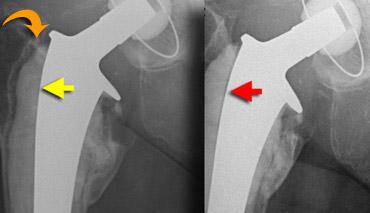

Che chắn ứng suất hay tiêu xương được thấy ở những vùng tương đối không chịu lực.

Các lực được truyền qua thân xương đùi tương đối cứng và biểu hiện là loãng xương ở vùng xương đùi gần với mỏng vỏ xương và tiêu xương cổ xương đùi.

Điều này được thấy ở phía trong là tiêu xương calcar, do calcar đã mất chức năng của nó (hình).

Nó còn được gọi là làm tròn calcar.

Lỏng cơ học biểu hiện dưới dạng vùng thấu quang lan tỏa.

Bệnh lý do hạt tiểu phân biểu hiện dưới dạng vùng thấu quang khu trú.

Bằng chứng của mòn polyethylene, biểu hiện dưới dạng vị trí bất đối xứng của chỏm xương đùi trong ổ cối nhân tạo, thường cùng tồn tại với bệnh lý do hạt tiểu phân.

Nhiễm trùng biểu hiện dưới dạng vùng thấu quang không đều kèm phản ứng màng xương, nhưng có thể khó phân biệt với lỏng khớp và bệnh lý do hạt tiểu phân. Trong các trường hợp điển hình, các dấu hiệu hình ảnh của lỏng khớp, bệnh lý do hạt tiểu phân và nhiễm trùng khá rõ ràng (hình).

Trong các trường hợp tiến triển nặng hơn, sẽ có tiêu xương không đều, không có viền xơ cứng, tiêu hủy vỏ xương và phản ứng màng xương.